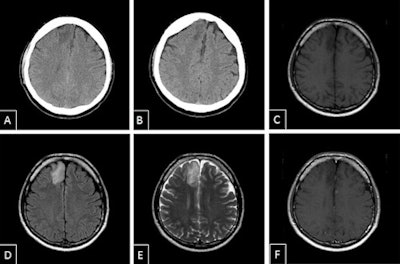

Low-grade malignant astrocytoma. Secondary finding of category 1 -- low-grade malignant astrocytoma. A and B: Axial noncontrasted CT, extensive hypodensity in right frontal region adjacent to the interhemispheric fissure. C: T1-weighted spin echo axial noncontrasted, hypodense lesion corresponding with noncontrasted CT. D and E: Fluid-attenuated inversion recovery (FLAIR), T2-weighted spin echo axial, signal alteration of the lesion. F: T1-weighted spin echo axial after gadolinium-containing contrast agent, no enrichment."In doing so, we keep discovering findings that have nothing to do with the trauma, but which require our attention," he said.